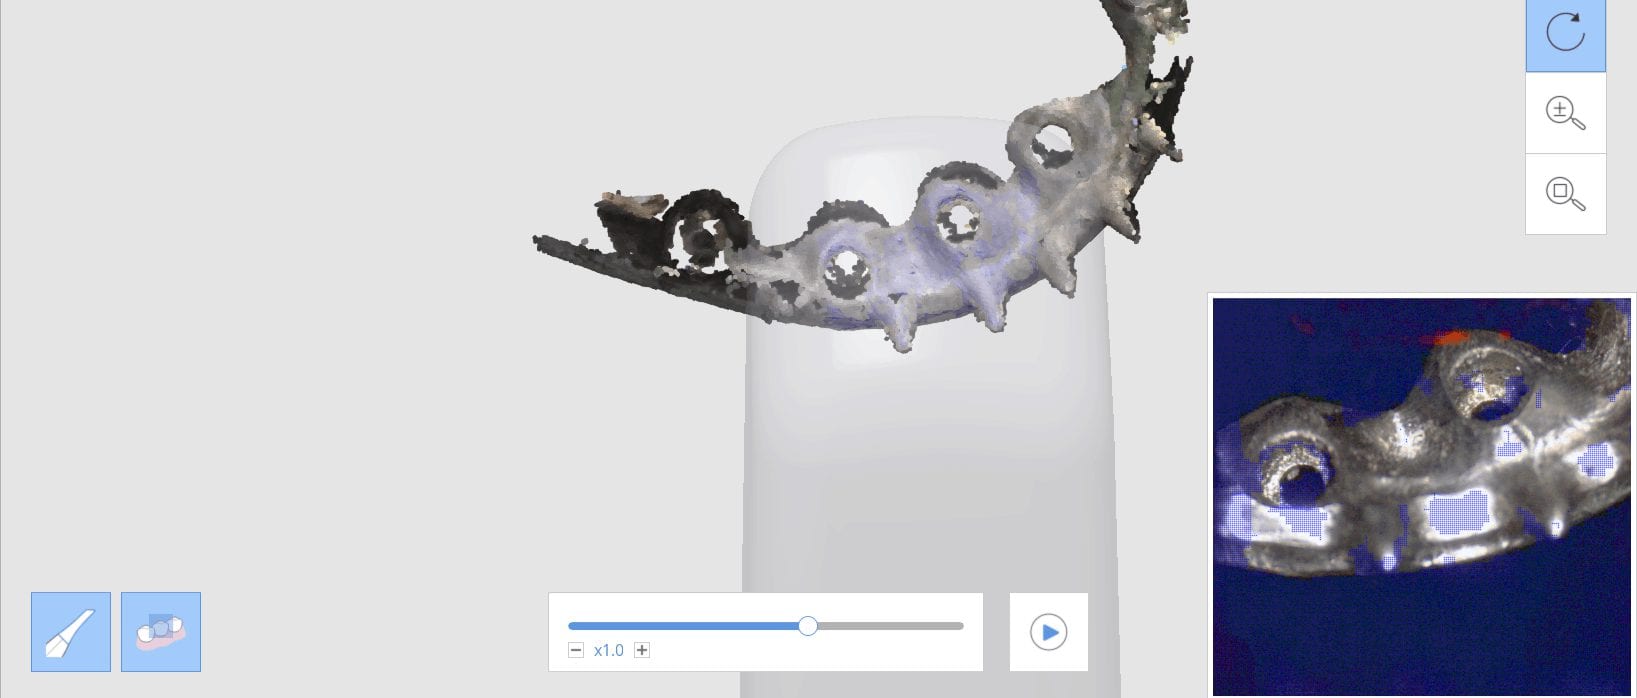

Milling A Lower Central Incisor in an eMax Size 12 Block on the VHF Z4 Milling Machine

March 29, 2019Time Stamps: This video is sped up at some points, but from the time the design was finished and it was sent to production, it tool less than 90 seconds […]